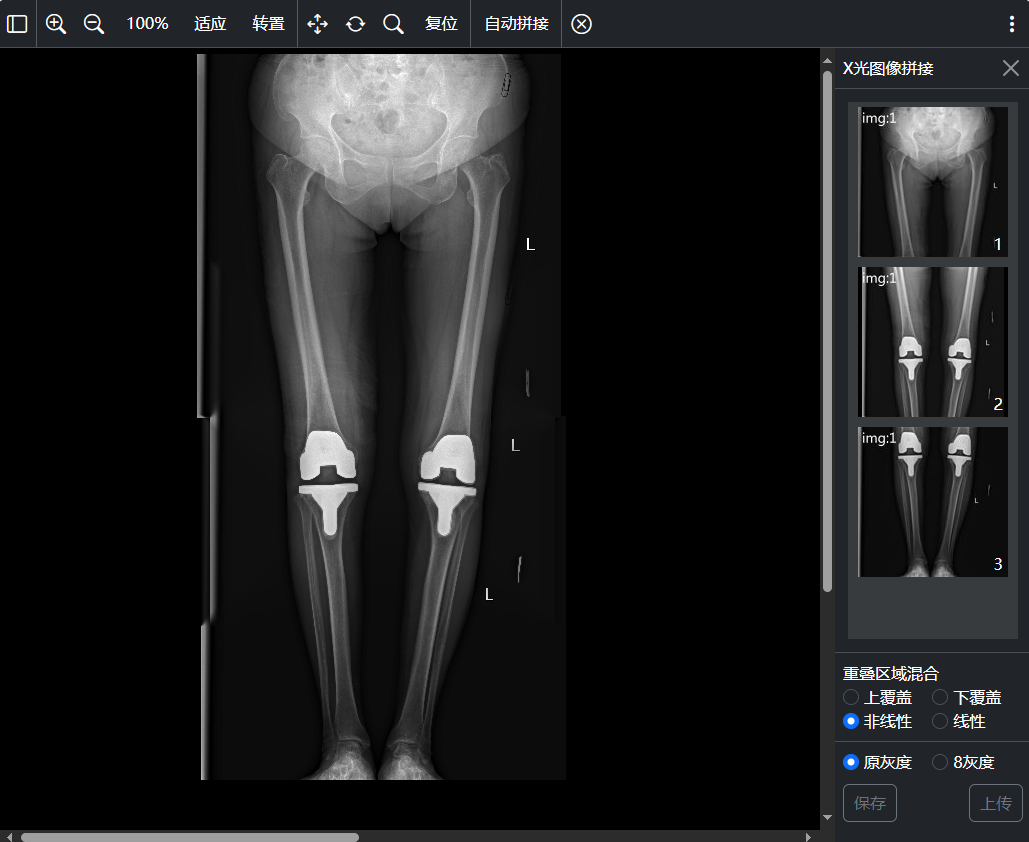

十一、X光图像 拼接

X光图像拼接窗口: 支持自动拼接、手工拼接、拼接图像保存、拼接图像上传功能;支持触发拼接图片上传完成事件

拖到序列缩略图到拼接显示窗口添加待拼接图像,显示再带拼接图像缩略图区域;

拖动待拼接图像缩略图到其它缩略图上可在其之前 / 之后插入拖动图像 或者 和 拖动图像交换位置;

拖动待拼接图像缩略图到拼接显示窗口则删除此待拼接图像;